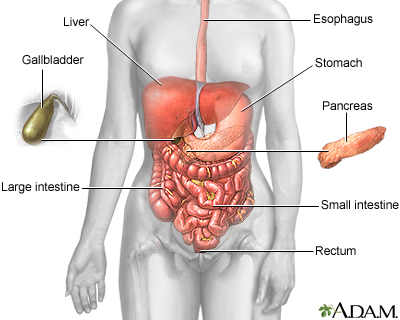

An abdominal CT scan makes detailed pictures of the structures inside your belly very quickly.

This test may be used to look for:

- Cause of blood in the urine

- Cause of abdominal pain or swelling

- Cause of abnormal blood test results such as liver or kidney problems

- Hernia

- Cause of a fever

- Masses and tumors, including cancer

- Infections or injury

- Kidney stones

- Appendicitis

The abdominal CT scan may show some cancers, including:

The abdominal CT scan may show problems with the gallbladder, liver, or pancreas, including:

The abdominal CT scan may reveal the following kidney problems:

Abnormal results may also be due to: